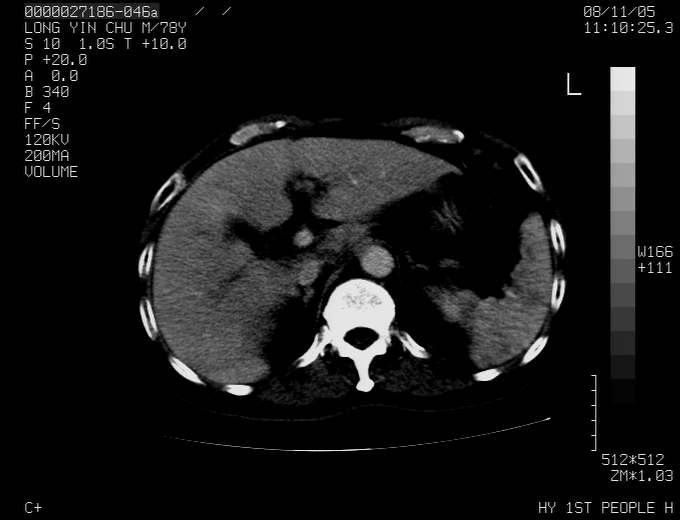

标题: CT16532:M78Y,肝脏病变,请会诊 [打印本页]

标题: CT16532:M78Y,肝脏病变,请会诊

腹胀,腹痛就诊,男性,78岁,外院b超未见异常。

肝ca,脾肾转移

支持脾肾转移瘤,双侧胸腔积液。

考虑弥漫性肝癌并脾及双肾转移.双侧胸水.

图片质量欠佳:多考虑:左侧肾癌。脾脏转移!胸膜转移!

肝脾肾转移瘤可能性大,左肾不除外梗塞,双侧胸水

考虑弥漫性肝癌并脾及双肾转移,双侧胸水。

考虑肝癌并双肾及脾脏转移;双侧胸腔积液。